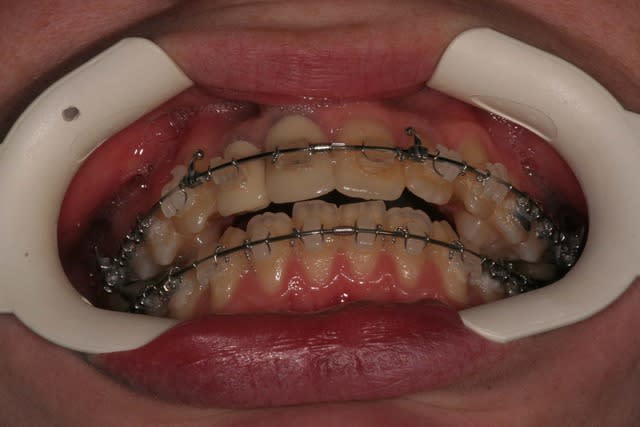

Voici le cas il y a un an

Elle était enceinte de 8 mois,

la voiture lui était déconseillée par son médecin,

j’ai donc décidé, avec l’accord de la patiente, de déposer (sans contention), car je ne voulais plus la laisser sans surveillance avec un matériel ortho en place

@+ Bjc.